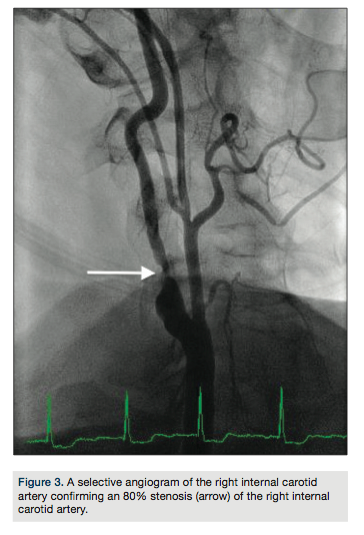

A 62-year-old male with history of atrial fibrillation on anticoagulation presented with a transient episode of left-sided weakness. Additional comorbidities included diabetes, heart failure with left ventricular ejection fraction of 30-35%, and coronary artery disease not suitable for revascularization. Computed tomography (CT) angiography did not reveal any focal infarcts but confirmed an 80% stenotic lesion in the right internal carotid artery and 60% stenosis of the right subclavian artery just distal to the right common carotid artery takeoff.

arch aortogram revealed a Type I aortic arch with no significant atheroma (Figure 1). A Simmons 2 catheter (AngioDynamics) was used to selectively engage the right common carotid artery by looping the catheter in the right coronary cusp. A stiff-angled Glidewire (Terumo) was then used as an anchor in the right external carotid artery (Figure 2A) and a Pinnacle Destination sheath (Terumo) advanced into the right common carotid artery (Figure 2B). Selective angiogram confirmed an 80% stenosis of the right internal carotid artery (Figure 3). An Emboshield distal embolic protection device (Abbott Vascular) was deployed in a straight segment in the distal right internal carotid artery. After pre-dilation with a Viatrac 4.0 x 20 mm